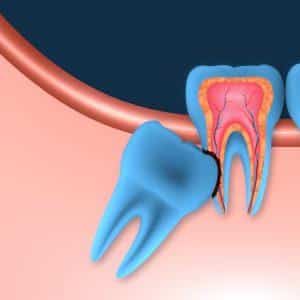

En muchas ocasiones, las muelas del juicio aparecen horizontales respecto al plano correcto de erupción e impactados en los segundos molares, aumentado el riesgo de que estos puedan padecer caries en zonas difícilmente restaurables y también tengamos que extraer.

Render muela del juicio